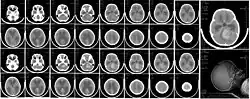

CT scan, showing a tumorous mass in the posterior fossa, giving rise to obstructive hydrocephalus, in a six-year-old girl | |